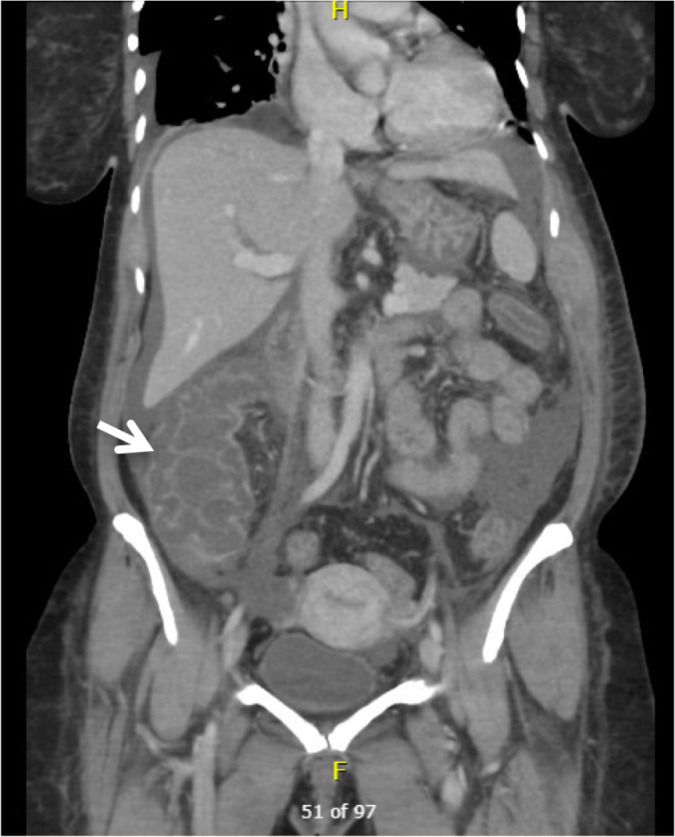

Lupus enteritis is a rare gastrointestinal complication of systemic lupus erythematosus (SLE) associated with significant morbidity and mortality. Rituximab, a monoclonal antibody targeting CD20-positive B cells, has shown promise in refractory SLE cases. We present a case of a 45-year-old female with SLE who developed lupus enteritis and experienced an unusually rapid and remarkable response to Rituximab. The patient presented with severe abdominal pain and distension. Within two days of Rituximab treatment, the patient's abdominal pain, distension, and associated complications resolved completely. This exceptional response challenges the typical timeline of Rituximab efficacy in SLE and highlights the need for further investigation into the factors influencing treatment response. Understanding the mechanisms underlying such rapid improvement may provide insights into SLE pathogenesis and guide therapeutic strategies for optimal outcomes.

Abstract Image